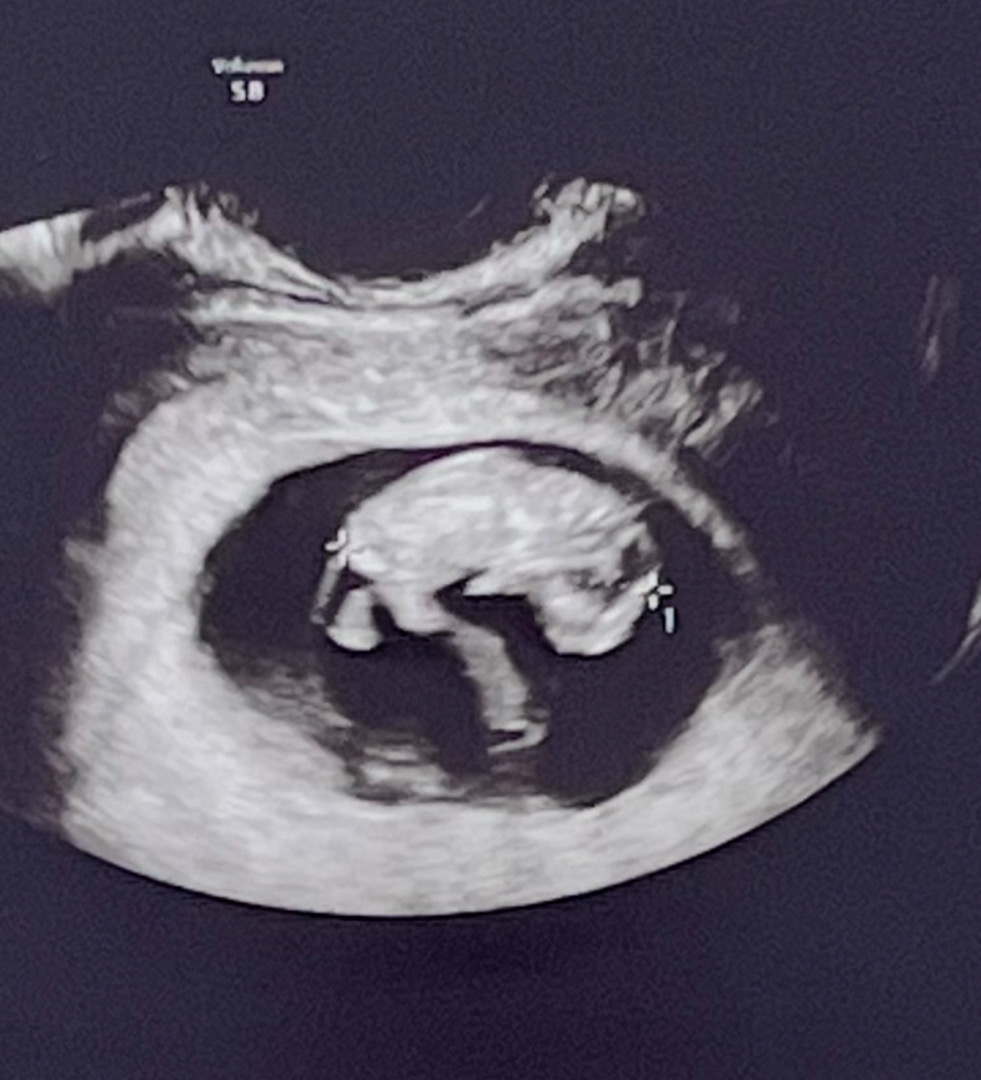

9주 4일차 젤리곰 옆모습 🐻

팔 다리가 생겼어요. 입덧 심할 때마다 촘파 사진 보면서 아기가 잘 크고 있다고 생각하면서 버텨요. 😂

아기를 자세히 보고 싶다고 하니까 오늘은 질 초음파로 봤어요! 8주차 때는 복부로 봤는데 확실히 질 초음파가 더 잘 보이는 것 같아요! 9주차까지만 질 초음파 보는 걸로 알고 있어용